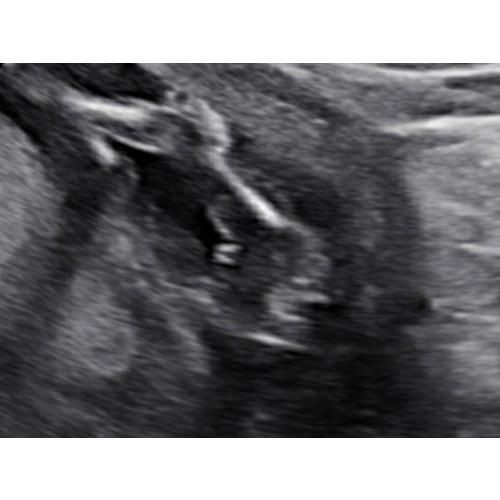

Lijkt inderdaad op een jongen. Zie onze echo wij krijgen ook een jongen. Die van ons is wel stuk duidelijk vindt ik zelf. Bij een meisje zie je een streepje en geen uitsteeksels

Duidelijk een jongen. Ik krijg een meisje en daarbij zag je duidelijk de hamburger, hier zie je echt balletjes.